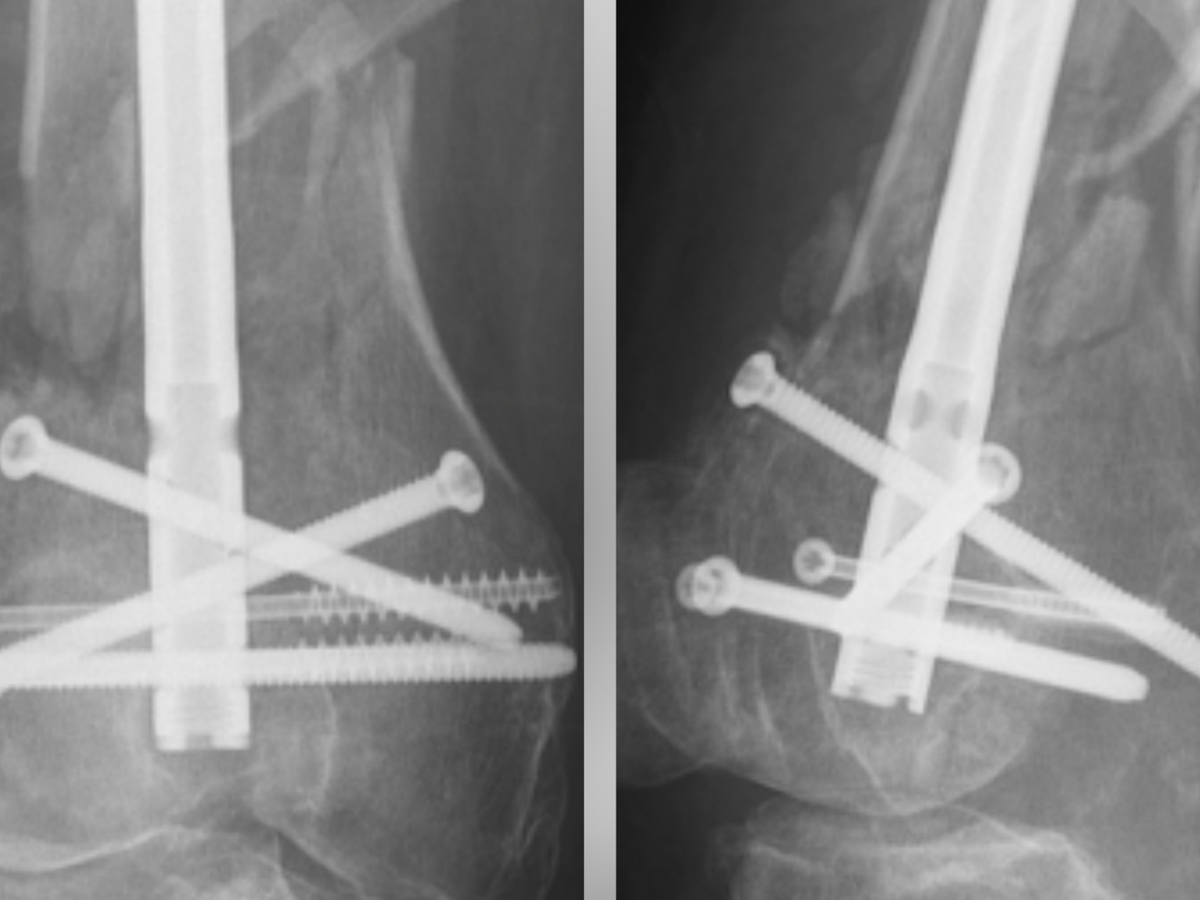

Hello friends.... the photo you see has 2 x-ray images of my right knee...as some of you know, I was involved in a very serious accident on January the 7th while riding my scooter. The result was a compound fracture of my right femur, shattered right kneecap and a torn ACL and further damage on the left leg. The other driver was 100% at faultI and EXTREMELY under insured. Eight hours of surgery, 12 days in the hospital....weeks later,I am STILL in a wheelchair and unable to walk...will not be able to work for at least the next two to three months, possibly longer....this is a LIFE ALTERING injury and I am struggling to afford rent, groceries, monthly bills, transportation to appointments and therapy. I am HUMBLY asking for your help by donating what you can and sharing as much as possible.